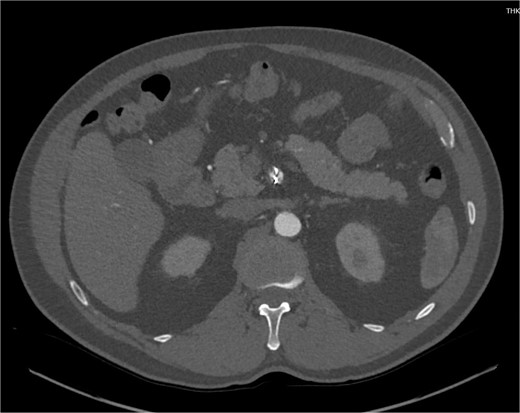

Despite medical management, the patient continued to have episodes of abdominal pain following discharge. One month after discharge, an outpatient mesenteric angiogram showed persistent SMA dissection and pseudoaneurysm. Coil embolization was performed to resolve the pseudoaneurysm. Following the procedure, the patient resumed anticoagulation therapy. The patient continued to follow outpatient studies with CTA indicating a normal SMA status post coil embolization of the pseudoaneurysm (Fig. 3).

CTA demonstrating interval embolization of SMA at site of prior thrombus and dissection.